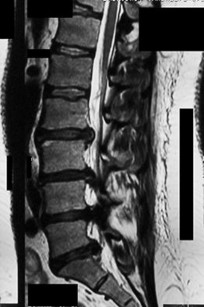

A 65-year-old female presents with neurogenic claudication and lower back pain. Radiographs reveal a grade I L4-L5 degenerative spondylolisthesis. Which of the following anatomical features is most characteristic of degenerative spondylolisthesis compared to isthmic spondylolisthesis?

Correct Answer: Sagittal orientation of the facet joints

Explanation:

Degenerative spondylolisthesis most commonly occurs at L4-L5 and is associated with a more sagittal orientation of the facet joints, which allows for anterior translation as the disc and joints degenerate without a pars defect. Isthmic spondylolisthesis involves a pars interarticularis defect, most commonly occurs at L5-S1, and is often associated with higher pelvic incidence.